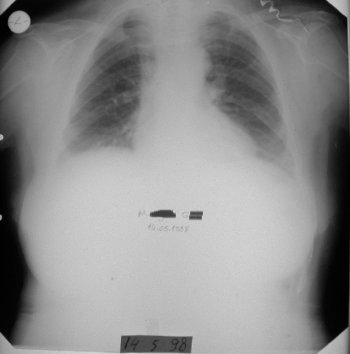

1995: 31 yaşındaki erkek hasta öksürük, ateş ve sırt ağrısı ile başvurdu.

Biyopsi sonucu "küçük hücreli anaplastik karsinom" teşhisi kondu.

Röntgende kitle küçülmüş durumda görüldü.

Röntgen tümörün tamamen kaybolduğunu gösterdi.